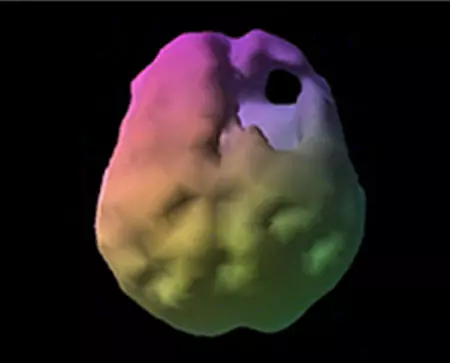

Concussion Brian Scan

SPECT (single photon emission computed tomography) is a nuclear medicine study that evaluates blood flow and activity in the brain. Basically, it shows three things: healthy activity, too little activity, or too much activity. The healthy surface brain SPECT scan on the left shows full, even symmetrical activity. The concussion scan on the right reveals unhealthy “holes” (areas that represent low blood flow and activity) in the damaged area..